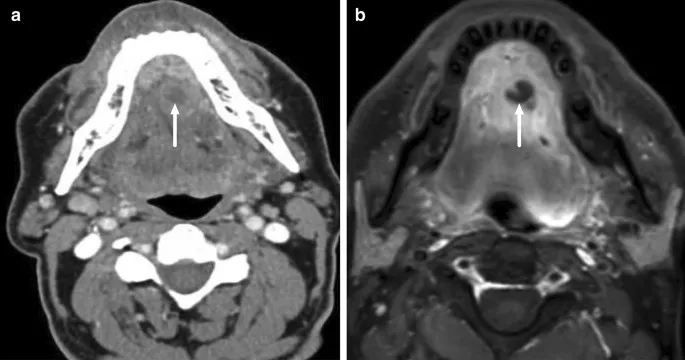

- CT with contrast: GOLD STANDARD. Defines extent, abscess.

- CT scan with contrast is key for diagnosis and extent.